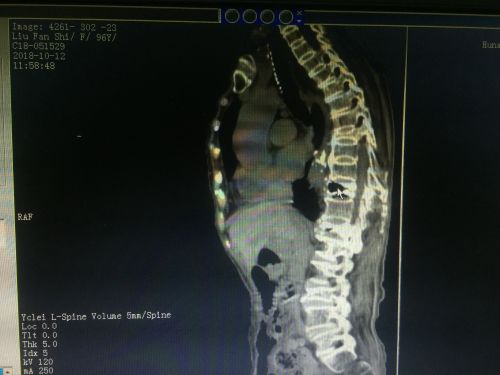

核磁显示,胸椎t10陈旧性骨折不愈合、t12新发压缩性骨折、腰l3陈旧性压缩性骨折。

入院进一步完善CT、核磁等检查后,老人被诊断为“胸椎T10陈旧性骨折不愈合、T12新发压缩性骨折、腰L3陈旧性压缩性骨折,重度骨质疏松症”。由于老人疼痛、活动受限症状典型,手术指征明确,10月16日,刘宏哲副主任医师和常磊主治医师等在局麻下为老人施行皮球囊扩张椎体后凸成形术(ercutaneous